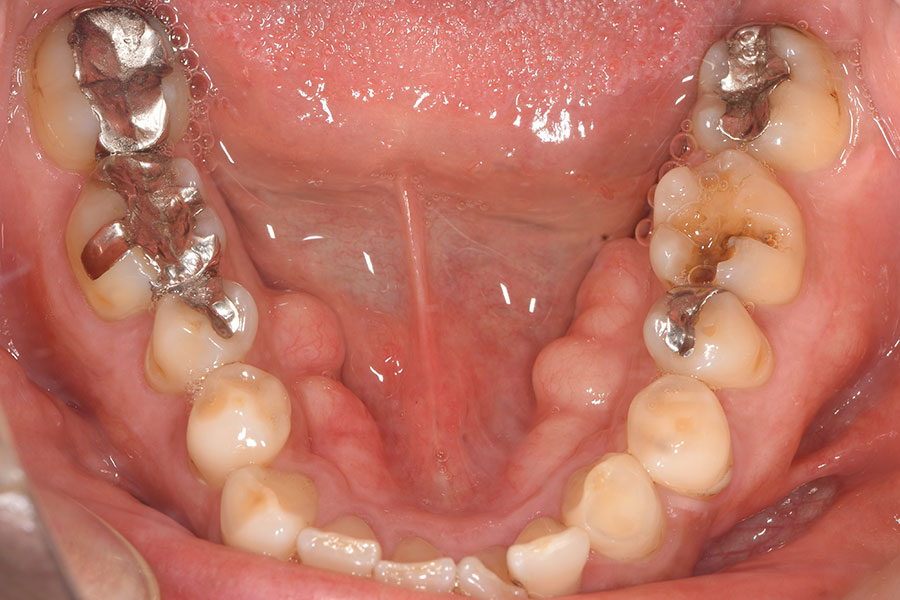

Before -下顎-

| 施術内容 | 金属アレルギー予防を目的に、金属フリーの自費補綴へ変更。適合性・清掃性・審美性の向上が得られています。 |

|---|---|

| 治療期間 | 約4ヶ月 |

| 費用 | ハイブリットクラウン ハイブリットインレー 693,000円 |

| リスク・副作用 | 治療にともない、歯の破折や歯質の削合、場合によっては抜歯が必要となることがあります。また、金属や補綴物を除去する際に、完全に除去できない場合もあります。 |